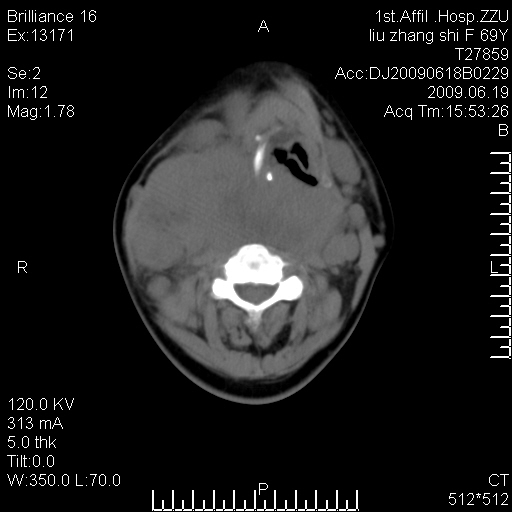

标题: CT26782:女,69岁,颈部占位,3天后公布病理结果。

【病理证实系列】女,69岁,颈部占位,有病理结果,3天后公布。(由于病例时间较久,临床资料不全,请网友见谅)本系列将有几百种常见、少见及罕见病例,均经病理证实。病例资料来自郑州大学第一附属医院。与网友共享,本人有空就发。

甲状腺癌并颈部淋巴结转移。感谢楼主的良苦用心,谢谢。

甲状腺癌并颈部淋巴结转移。

需与鼻咽癌鉴别!

支持甲状腺癌广泛侵及周围结构并颈部淋巴结转移。

鉴别:淋巴瘤、恶性神经源性病变、恶性纤维组织细胞瘤。

病理结果:颈部非霍奇金淋巴瘤。

右侧甲状腺确实有问题